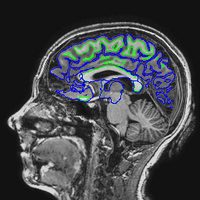

EPI images are significantly distorted relative to true brain anatomy. This is a problem because activation maps created from EPI images are overlaid on T1 images (or cortical surface models created from T1 images) which reflect the true anatomy. The following images show a T1 image with outlines for the outer boundary of gray matter (blue line) and white matter (green line).

Here are uncorrected EPI images with the same boundaries overlaid.